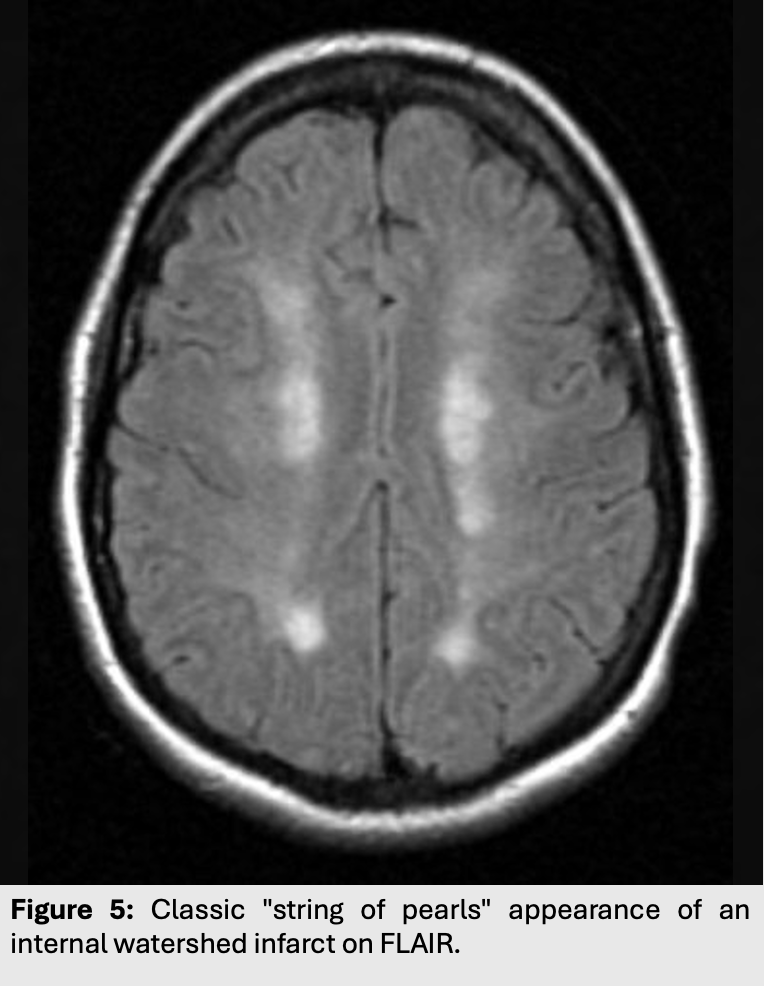

Figure 5: Classic "string of pearls" appearance of an internal watershed infarct on FLAIR.

Figure 4: Cortical versus internal border zone appearances. Classically, internal watershed infarcts present as a “string of pearls” whereas external watershed infarcts have a wedge like appearance and involves the cortex.